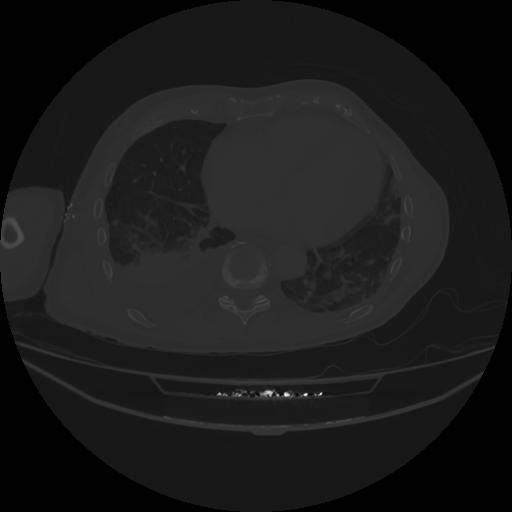

5 CUERPO,CE,Vol,1.0,CUERPO,,